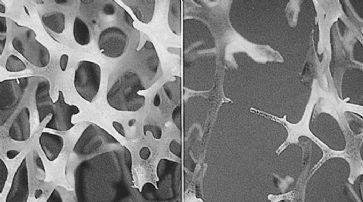

Die A*STAR-Forscher können mit ihrer neuen Methode monoklonale Antikörper effektiver von Nanopartikeln säubern. «Unser Nanopartikel-Verfahren ist schneller als die herkömmlichen Methoden», sagt Studienleiter Pete Gagnon. Monoklonale Antikörper gegen Ebola

Das Nanopartikel-Verfahren ist schneller als die herkömmlichen Methoden. (Symbolbild) /

Die Pharmaindustrie benötigt die monoklonalen Antikörper für die Herstellung verschiedener Medikamente. Das Forscherteam vom A*STAR Bioprocessing Technology Institute in Singapur hat ein Verfahren unter Miteinbeziehung von Polyethylenglykol entwickelt, das bewirkt, dass die Antikörper auf der Oberfläche der stärkebeschichteten, magnetischen Nanopartikel abgestossen werden.

Erste Ergebnisse bereits nach Stunden

Die Partikel werden in einem magnetischen Feld gesammelt. Die Verunreinigungen werden weggespült und die gereinigten Antikörper durch das Entfernen des Polyethylenglykols zurückgewonnen. «In der pharmazeutischen Industrie liegt die Norm bei fünf bis acht Zyklen, bis die monoklonalen Antikörper gereinigt sind. Das neue Verfahren benötigt nur einen Kreislauf, der nur ein paar Stunden dauert», erklärt Gagnon.